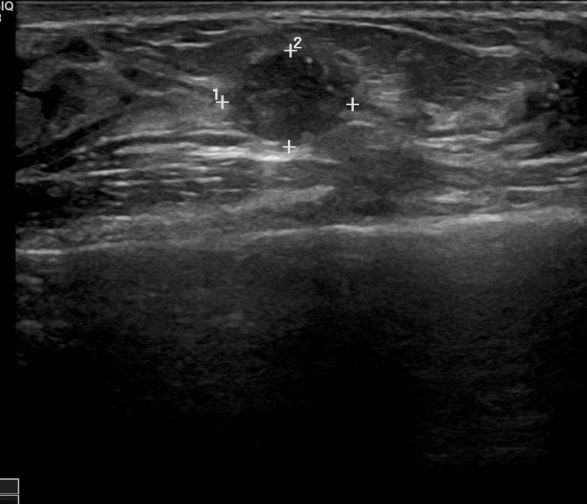

외부검사상 이상소견으로 내원하신 40대 여성분으로 우측유방 조직검사시행후

유방암으로 진단되었읍니다.